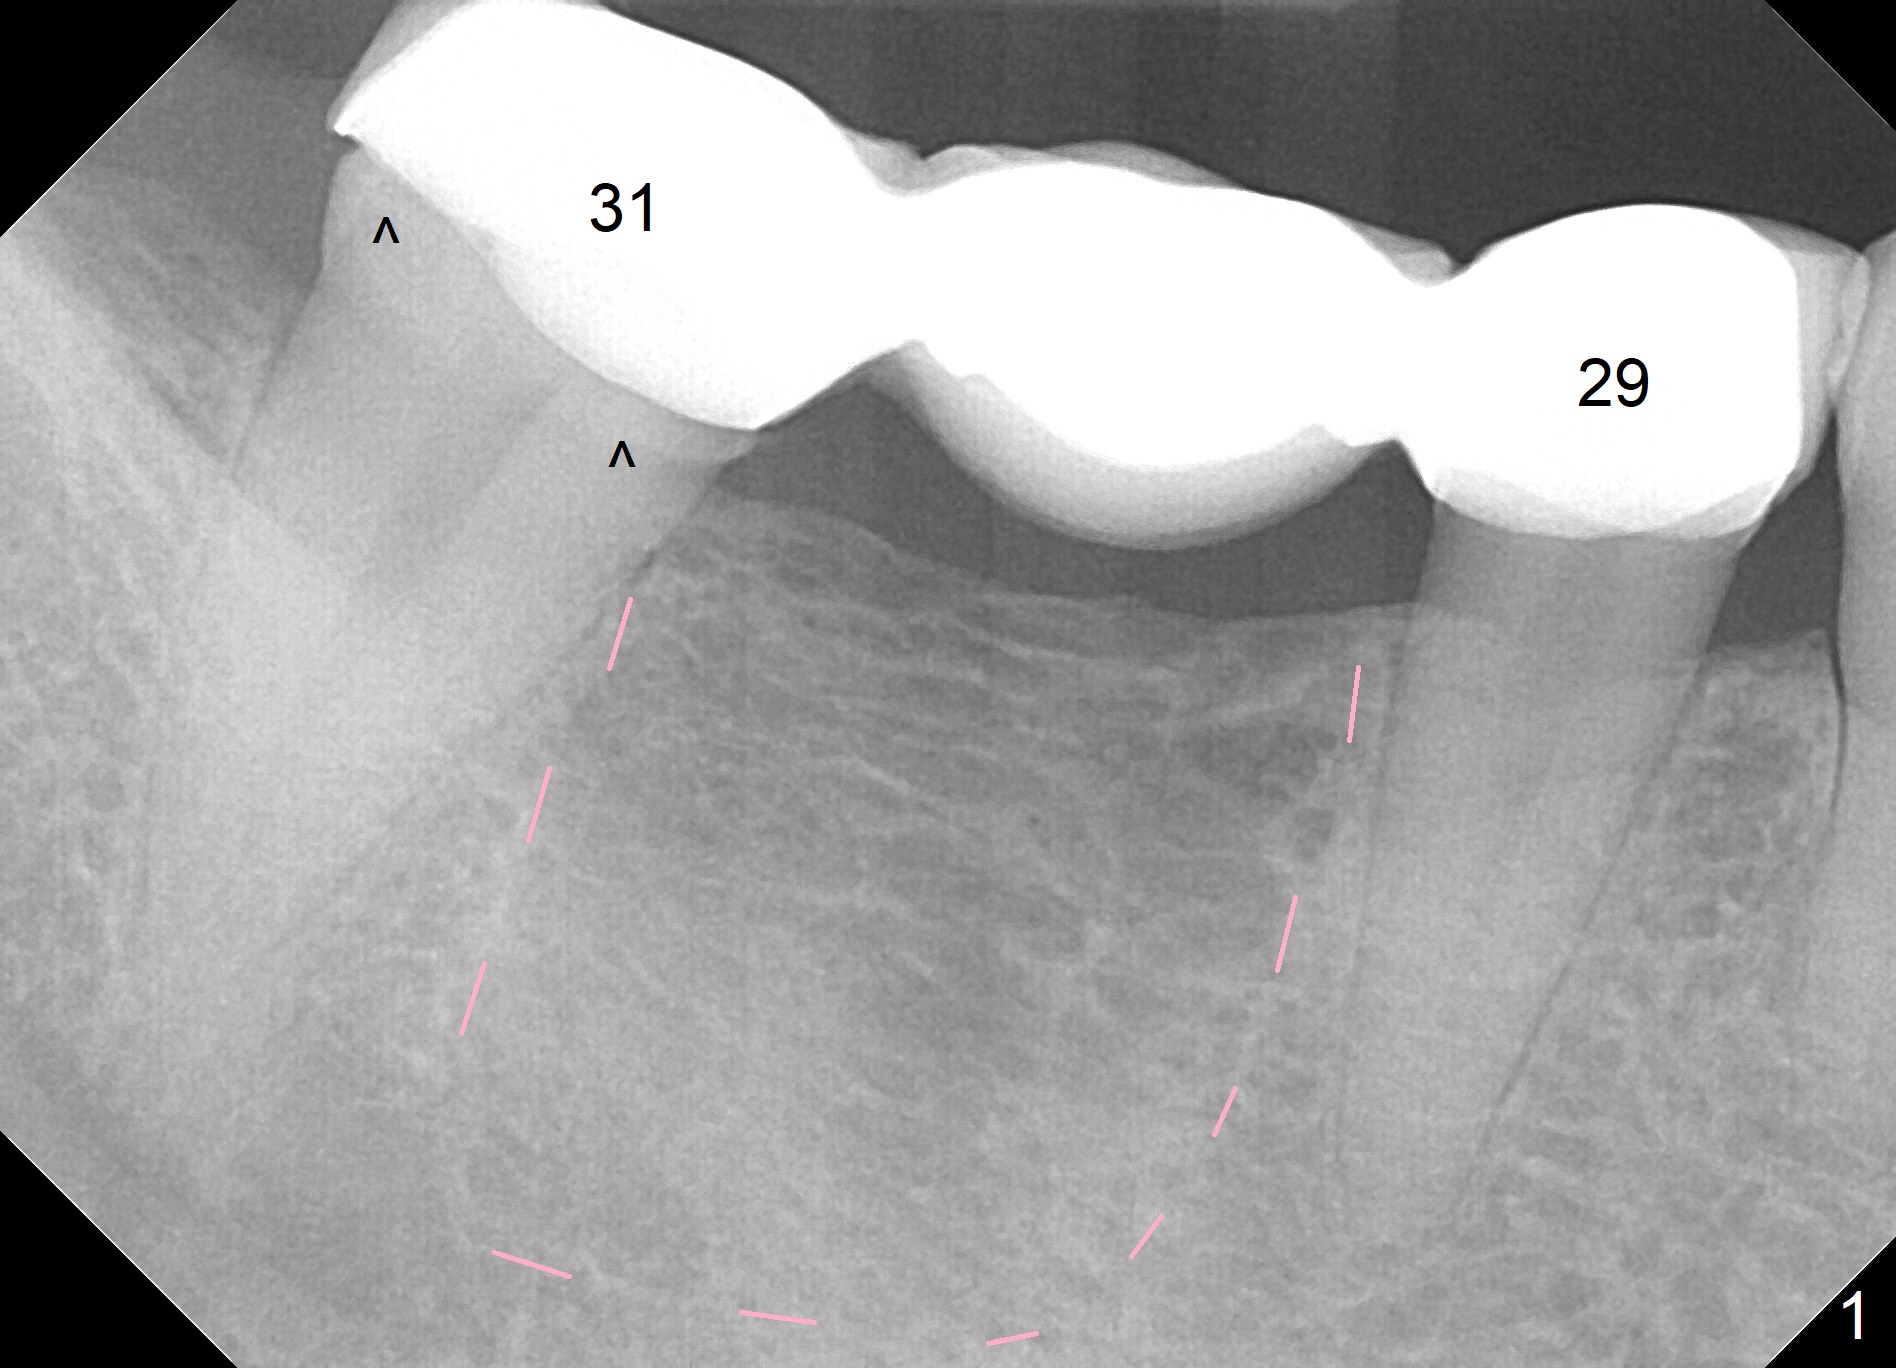

A 38-year-old woman has a loose FPD in the lower right quadrant (Fig.1). The retainer at #31 appears to have open margin (Fig.1 ^) or the abutment has caries (Fig.2 arrowheads). The FPD will be sectioned between #29 and 30. The abutment at #31 needs at least a crown, while an implant will be placed at #30. The bone density at the site is low (Fig.1 pink dashed line). The latter may be due to narrow bone buccolingually. If the ridge atrophy is moderate (e.g. 4 mm (implant positioners)), bone expansion will be executed (Bone Expander Kit or IBS Kit) and a 3.8, 4.1 or 4.5 mm implant will be placed. If the atrophy is severe, the ridge top will be reduced until the ridge is ~ 4 mm, two of 2.5 or 3.0 mm 1-piece implants will be placed (Fig.2). A splinted provisional will be fabricated at #30 and 31.